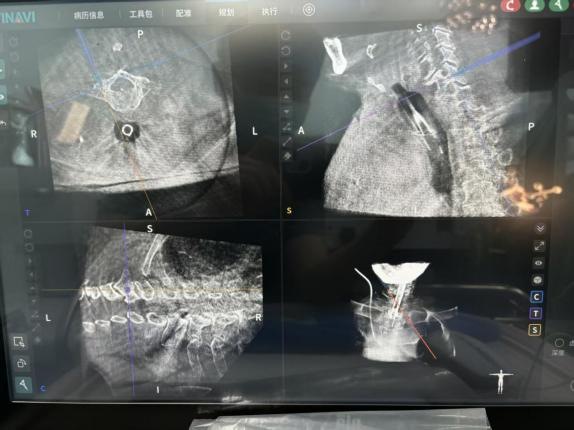

术前,机器人为每一枚椎弓根螺钉的置入规划最优路径,打造精准手术“蓝图”;术中,实时导航辅助操作,全程监测、调整螺钉置入方向,从矢状位、冠状位、轴位多维度把控置钉角度,有效规避了神经、血管损伤的风险,大幅降低了手术潜在风险。

同时,机器人还能实现术中即刻扫描,螺钉位置清晰可见,彻底解决了传统透视的遮挡难题。